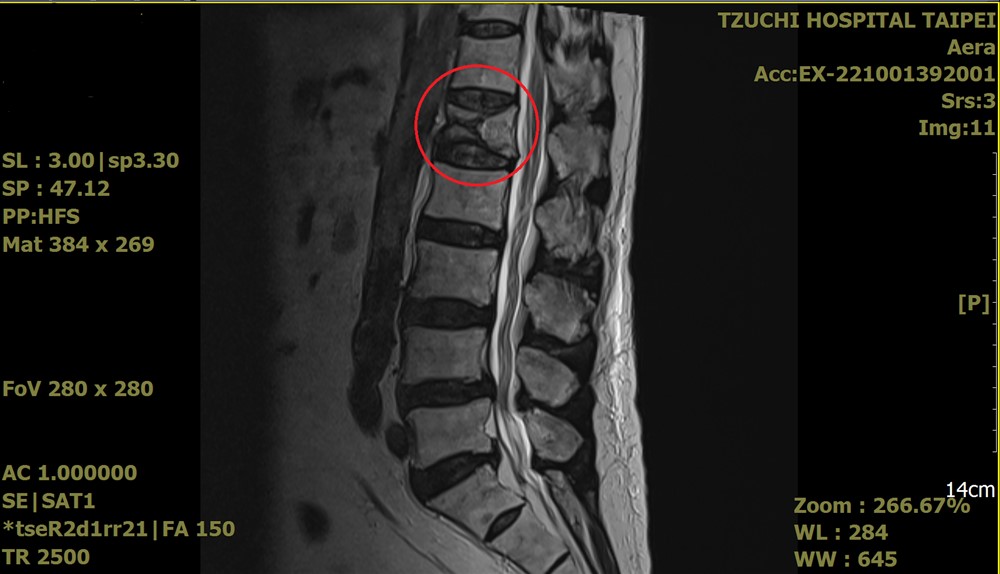

來到台北慈濟醫院就診神經外科,洪立偉醫師透過影像及理學檢查,發現陳先生的腰椎第一節出現壓迫性骨折,與家屬討論治療方案後,決定執行「微創骨水泥手術」,術後隔日陳先生已能下床自行活動,恢復正常生活。

術前核磁共振影像顯示,腰椎第一節呈現壓迫性骨折。圖/台北慈院提供